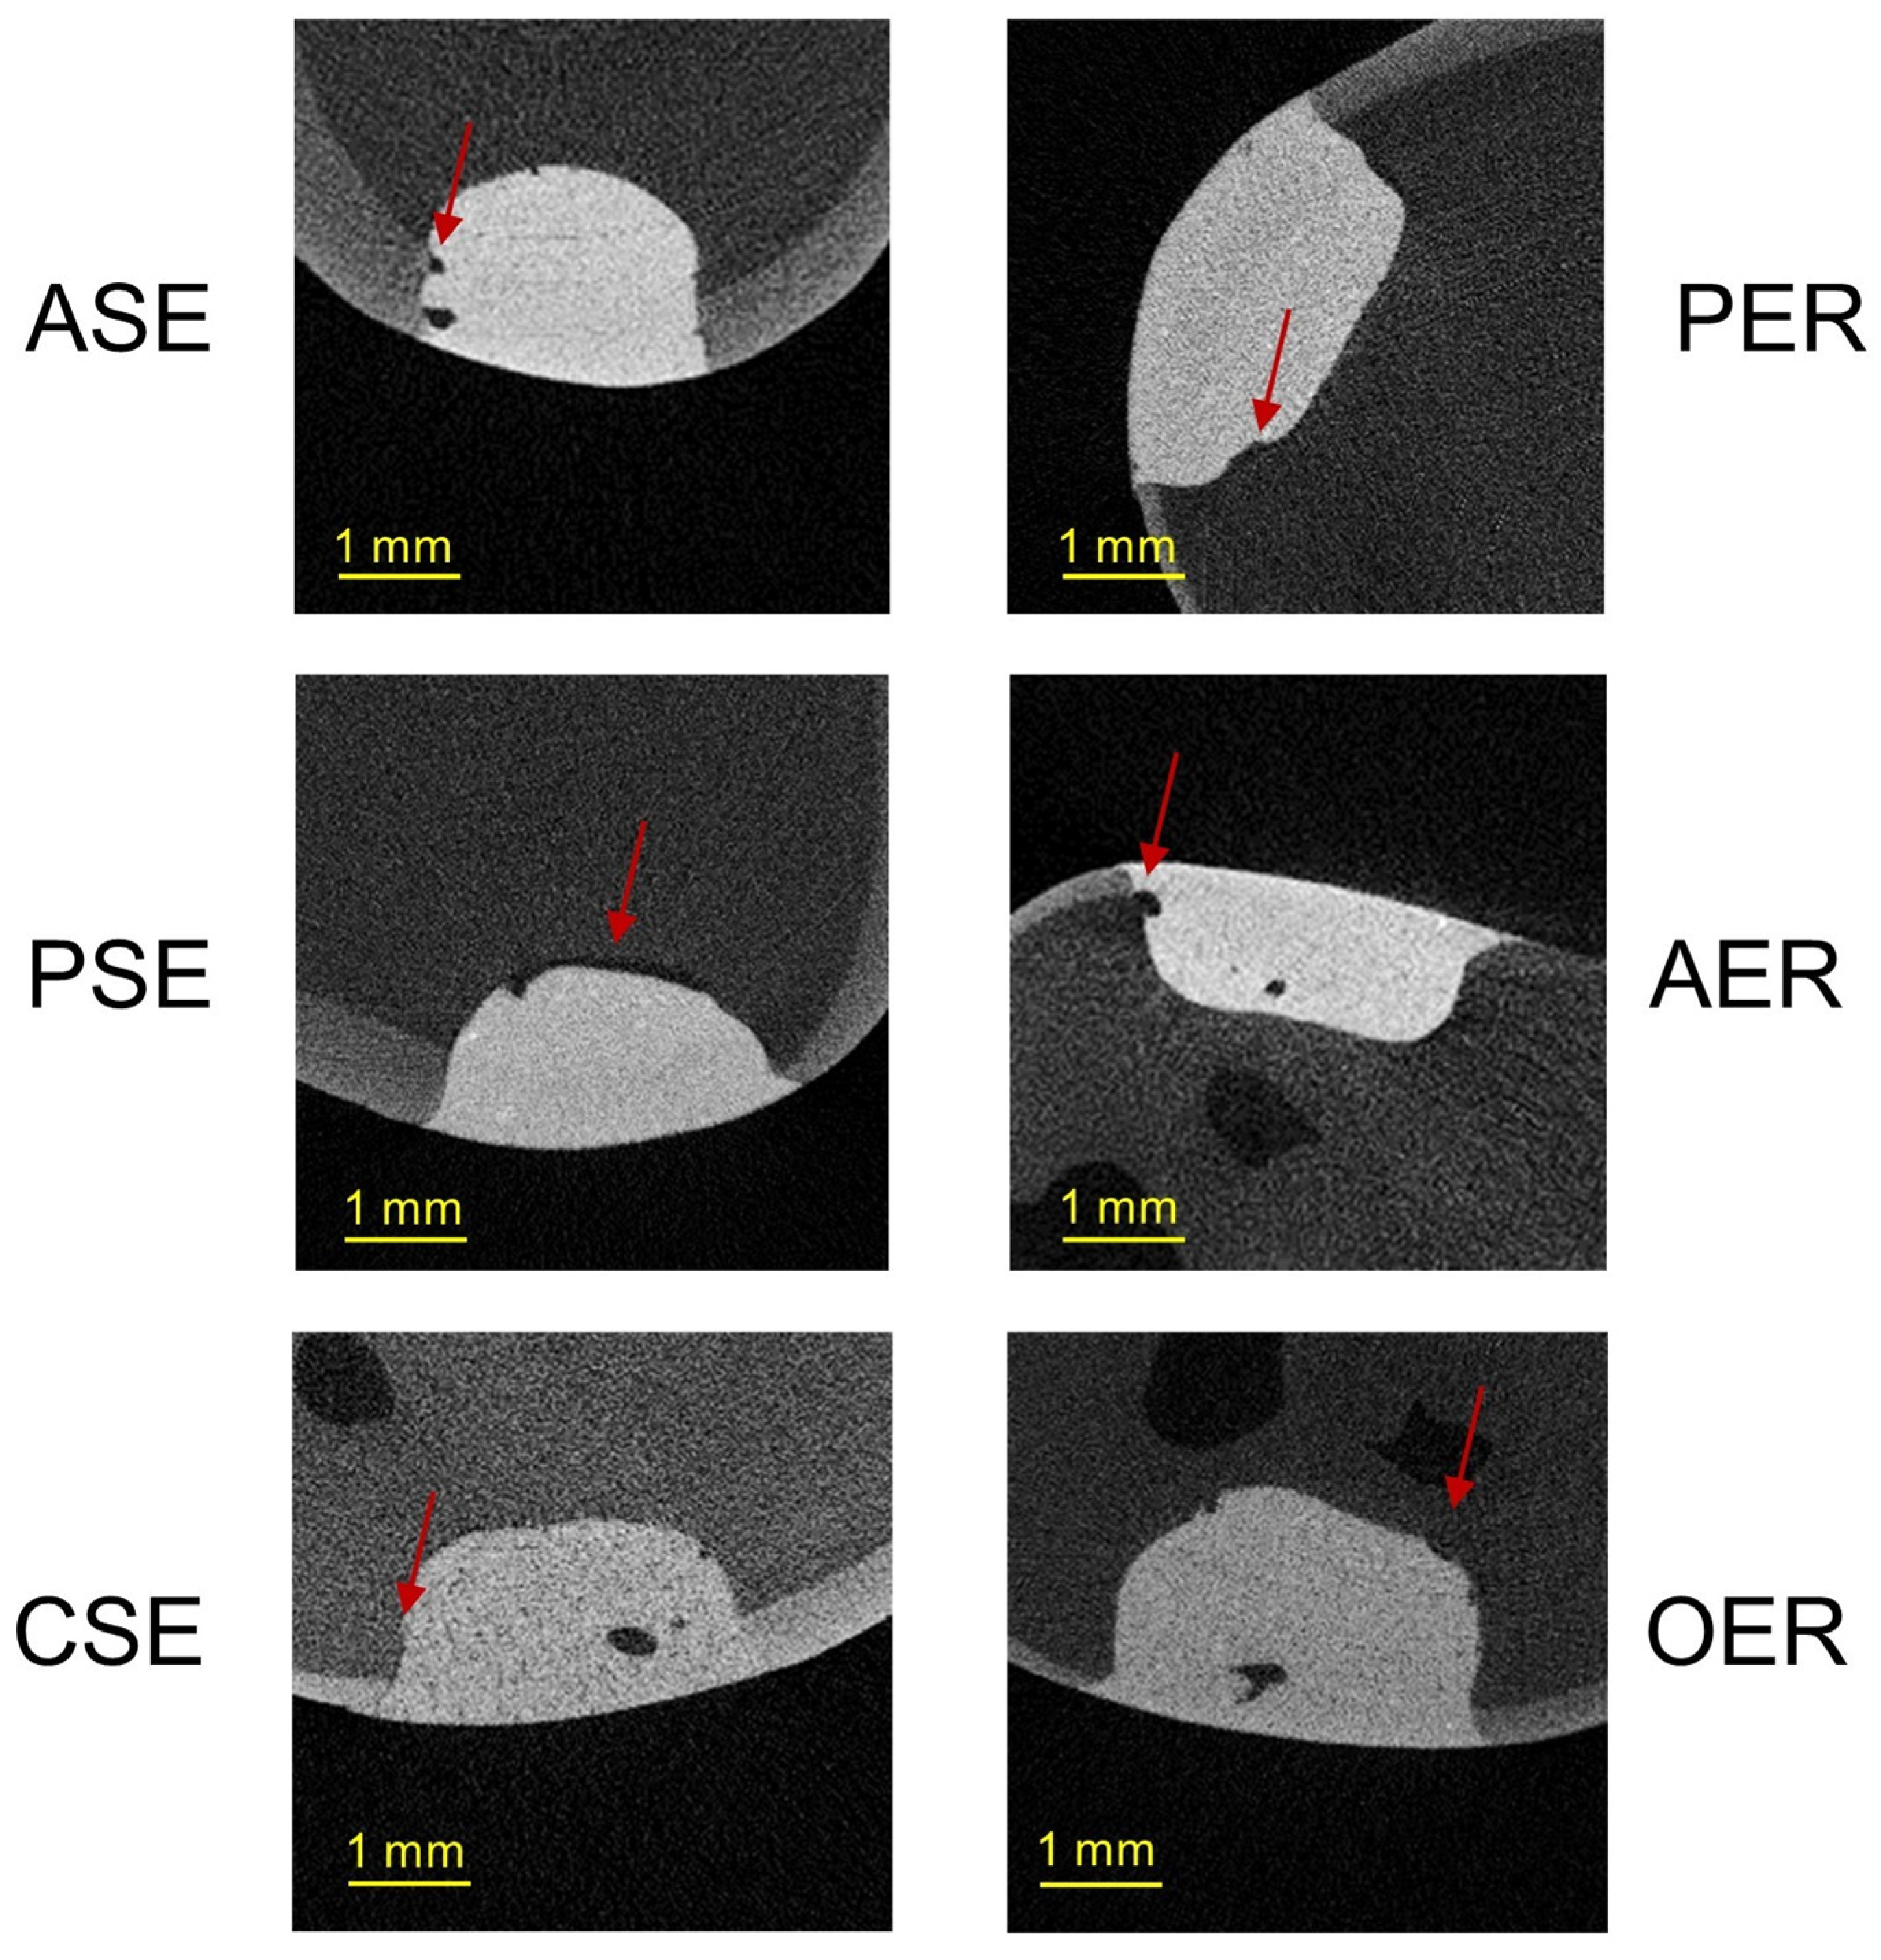

3.2. Gap Volumes at the Tooth–Filling Interface of the External (EGV) and Internal Parts (IGV) of Cavities

4.4. Gap Volumes at the Tooth–Filling Interface of the External (EGV) and Internal Parts (IGV) of Cavities